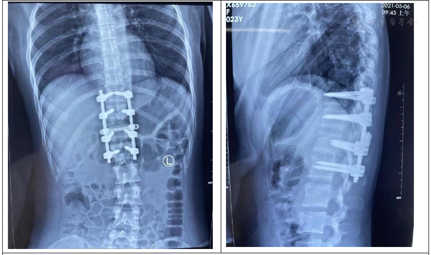

患者,女性,23岁,于2021年4月29日从约2 m高处坠落致伤胸腰部,当即出现腰背部疼痛伴活动受限,双下肢运动感觉功能减退,运动功能部分丢失。病情呈渐进式加重,至受伤后10 h,双下肢感觉运动功能完全丧失,骶残留消失。被急送至西安市红会医院急诊科,急诊医师以"胸12椎体骨折伴脱位"之诊断收入住院,于2021年4月29日急诊在全身麻醉下行"胸12椎体骨折脱位切开复位椎板减压椎板间植骨融合内固定术",术后患者双下肢感觉障碍较术前改善,运动功能部分改善,患者及家属为求进一步治疗,请我科会诊,后以"脊髓圆锥损伤(ASIA C型),胸12椎体骨折伴脱位术后疼痛,腰3椎体压缩性骨折"收住我科。

患者术后(1周)开始接受康复及药物治疗,目前术后3个月,已完成3个疗程治疗,门诊随访,患者大小便功能恢复正常,双下肢轻触觉、针刺觉恢复,双下肢肌力由Ⅲ-级恢复至Ⅳ级,能自主上下楼梯,蹬自行车,ADL自主功能恢复。